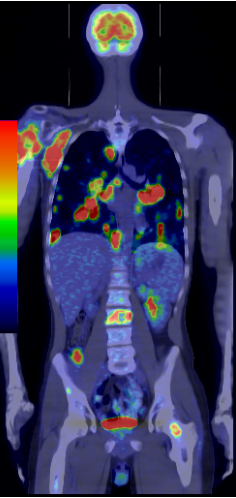

Among the general characteristics of isotope examinations, besides the ability to gain functional information, it is important to mention that – derived from the tracer principle – the examinations are highly sensitive, so the pathological processes can be detected at an early stage. SPECT is able to detect nano-molar radiotracer concentrations, while PET picks up signals coming from pico-molar radiopharmaceutical quantities. The higher sensitivity is due to the fact that functional alterations of metabolism usually precede detectable morphological changes of the tissues, thus functional studies allow earlier and more precise diagnostics. Another aspect of higher sensitivity is that in an optimal scenario, the biologic contrast between normal and pathologic function is very high. Therefore, signal intensity of a normal tissue process will be much lower than that of a pathologic one, making them easily distinguishable on the image. (Figure 2.)

Test iframe

2. FDG PET Maximum Intensity Projection (MIP) image. There is a large biological contrast between the normal and the pathologic tissues. Right sided breast cancer, ipsilateral metastatic lymph nodes and multiplex metastases in the lung. Physiologically elevated FDG uptake is seen in the brain, salivary glands, tonsils, liver and the spleen as well as in the bone marrow and at certain segments of the intestines. Also, there is increased FDG activity in the kidneys and the urinary bladder due to excretion.